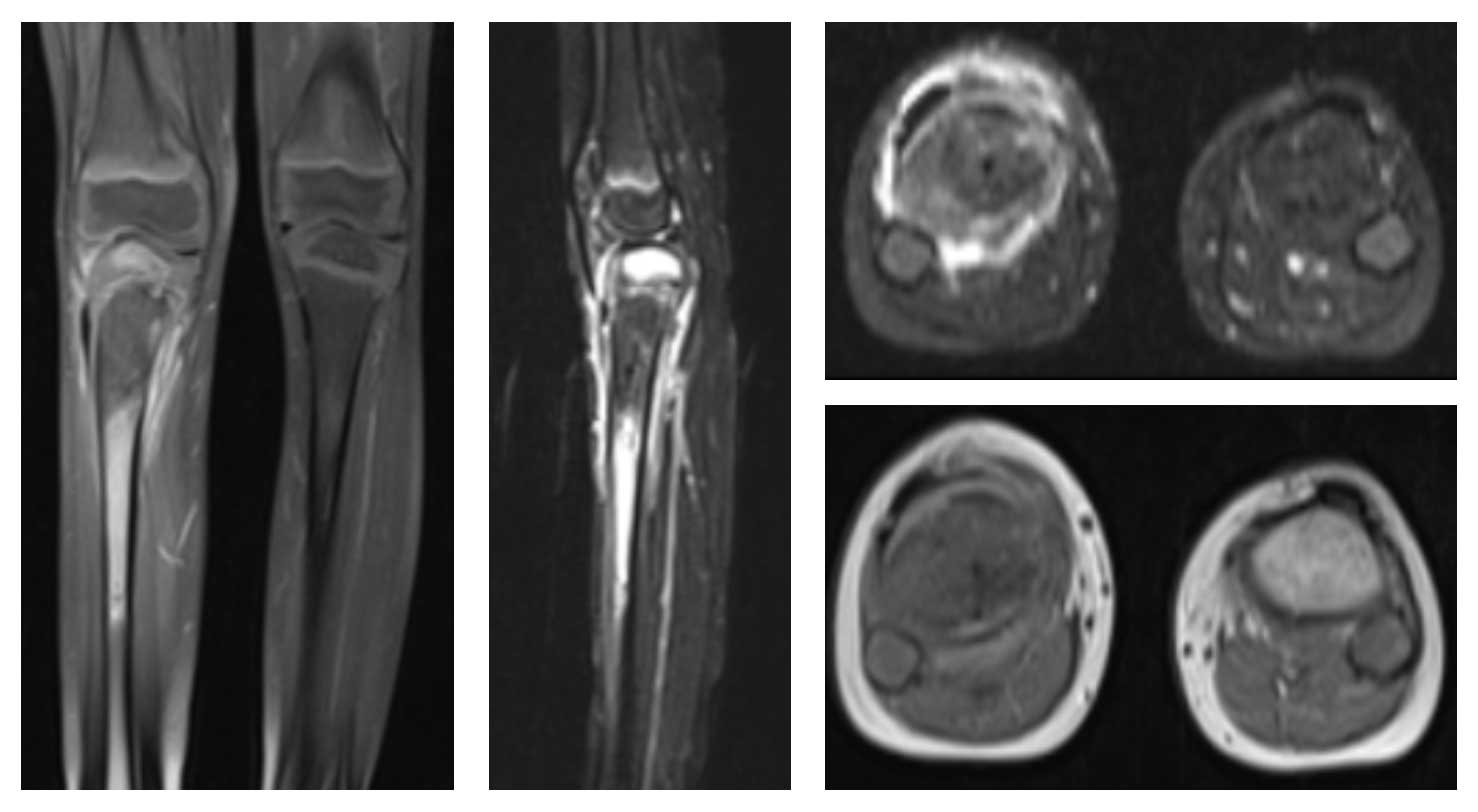

Ameliyat Öncesi: MR’da ek olarak çevreleyen yaygın ödem görülmekte.